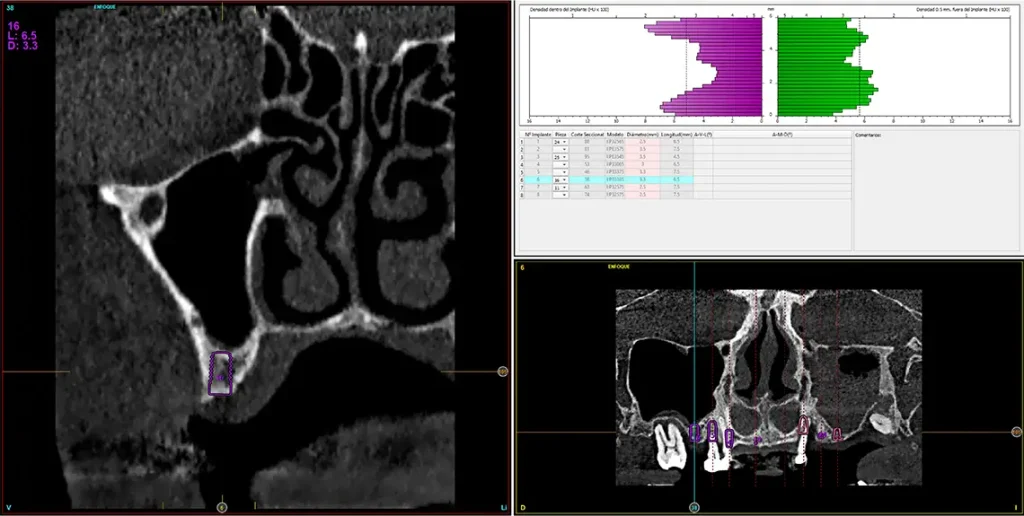

Para realizar una planificación precisa del caso y determinar el volumen óseo residual antes de la cirugía implantológica, se realiza un estudio mediante tomografía de haz cónico (cone-beam) y se visualiza mediante un software específico (BTI-Scan IV). Esta exploración permite medir con exactitud la altura y anchura de la cresta ósea, así como evaluar la densidad de las zonas en las que se prevé colocar los implantes, facilitando así una planificación quirúrgica fiable y ajustada a las necesidades anatómicas del paciente44–47. En las imágenes del cone-beam de control, observamos en el segundo cuadrante una atrofia vertical extrema, con zonas de menos de 4 mm de altura, donde se planifican implantes de 4,5 mm de longitud que serán colocados mediante el procedimiento de elevación transcrestal con fresa de corte frontal y con hueso autólogo obtenido del fresado embebido en PRGF-Endoret como material de injerto. Esta técnica, descrita por nuestro grupo de estudio, nos permite realizar un abordaje seguro del seno maxilar con una escasa invasividad (figs. 8-10)9,25,29,36.

Figs. 9-10. Medida de la zona con mayor atrofia del segundo cuadrante menor a 4 mm de altura y planificación del implante de 4,5 mm de longitud que será colocado mediante el procedimiento de elevación transcrestal anteriormente descrito.